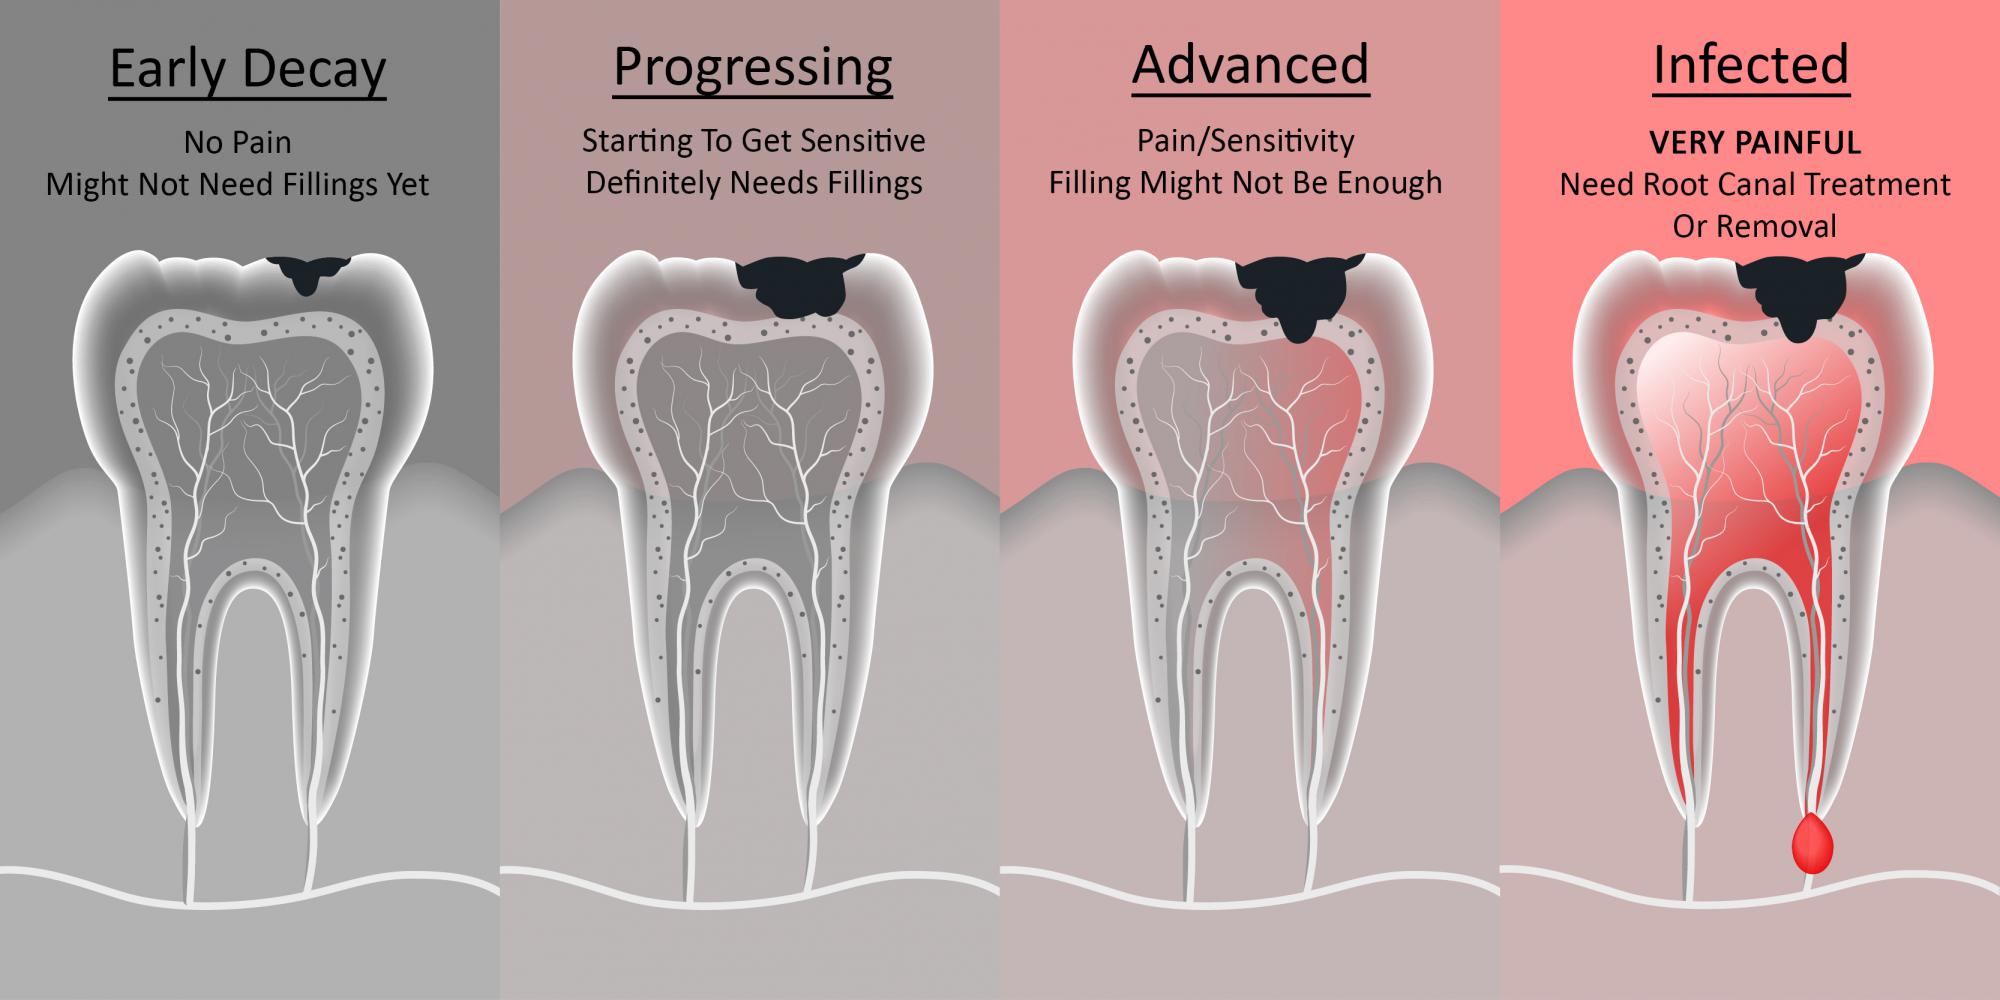

- Inflammation and Infection: When decay reaches the pulp (the innermost part of the tooth containing nerves and blood vessels), it can cause inflammation (pulpitis) or even an infection leading to an abscess. This inflammation or infection puts pressure on surrounding nerves, and the pain can radiate upwards to your head.

- Referred Pain: Our brains can sometimes get confused about where pain is coming from. Pain originating in a decayed tooth can be "referred" to other areas of the head, such as the temples, forehead, or even around the eye. This means the actual source of the pain is the tooth, but you feel it elsewhere.

- Muscle Tension: If you're constantly favoring one side of your mouth because of a painful tooth, or clenching your jaw due to discomfort, it can lead to muscle tension in your jaw, neck, and shoulders. This tension can easily trigger tension-type headaches.